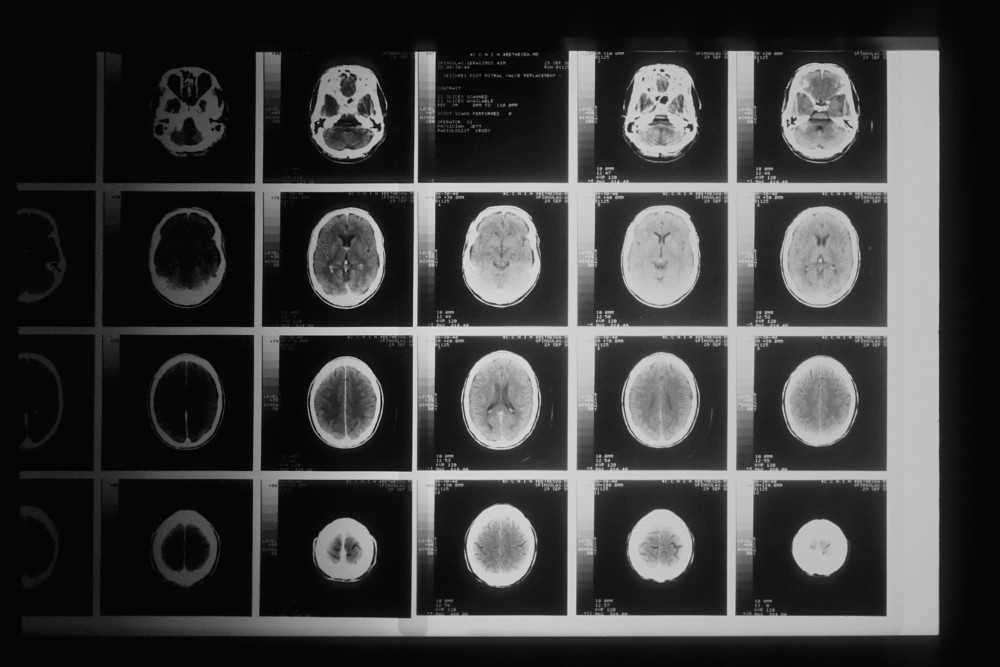

Sclérose en plaques IRM : Outil central du diagnostic

L’imagerie par résonance magnétique (IRM) a révolutionné le diagnostic de la SEP. Cette technique non invasive permet de visualiser avec précision les lésions démyélinisantes du système nerveux central.

En SEP, l’IRM recherche principalement :

- Des plaques hyperintenses en séquence T2, témoins de zones de démyélinisation

- Des lésions prenant le contraste après injection de gadolinium, signe d’une inflammation active

- La localisation périventriculaire, juxtacorticale ou infratentorielle des lésions, typique de la SEP

L’IRM permet d’observer l’évolution silencieuse de la maladie, même quand le patient se sent bien. En effet, elle permet parfois de détecter des lésions asymptomatiques, révélant une activité inflammatoire invisible cliniquement. Le suivi par IRM, généralement annuel dans les premières années après le diagnostic, permet d’évaluer l’efficacité des traitements et d’adapter la prise en charge si nécessaire.